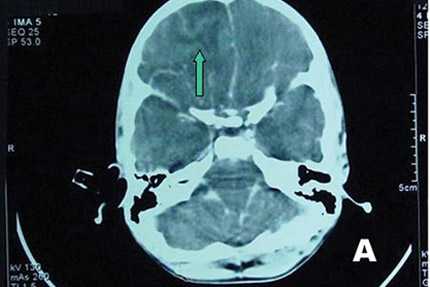

Bác sĩ Phan Văn Hiếu, Giám đốc Trung tâm Pháp y TP. HCM khẳng định: Mẫu xét nghiệm từ bệnh nhi Tài Tiền (6 tuổi, TP.HCM) cho kết quả dương tính với amip ăn não Naegleriafowleri. Amip này đã tồn tại trong não bé với thời gian khá lâu, khoảng ít nhất 1 tháng. Amip này tấn công phần não trắng và phần chất xám. Vùng áp xe ngả vàng.